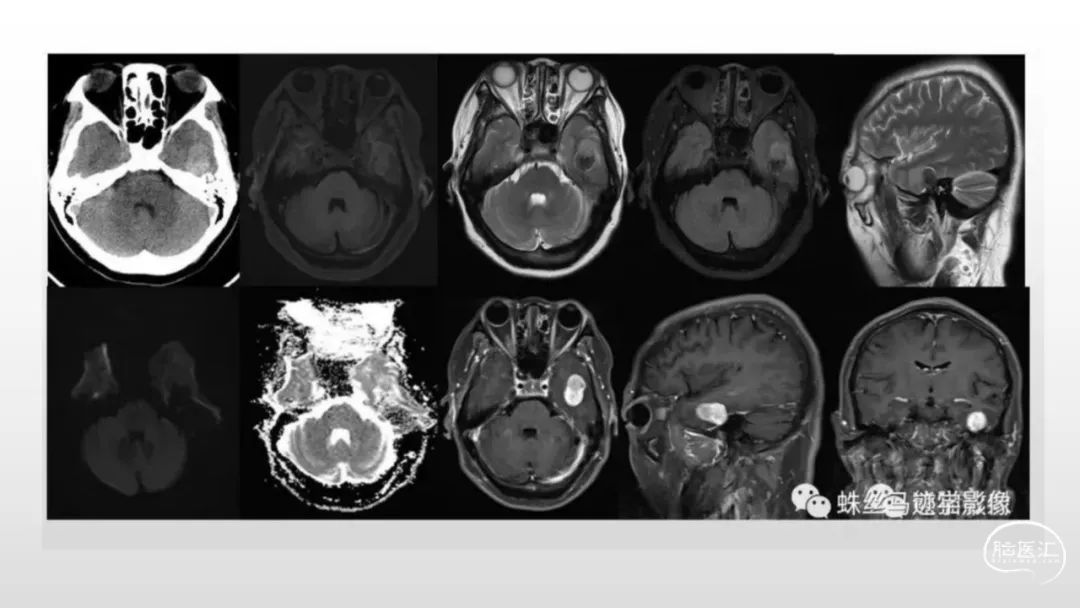

颅脑影像诊断基础知识讲座:脑膜病变